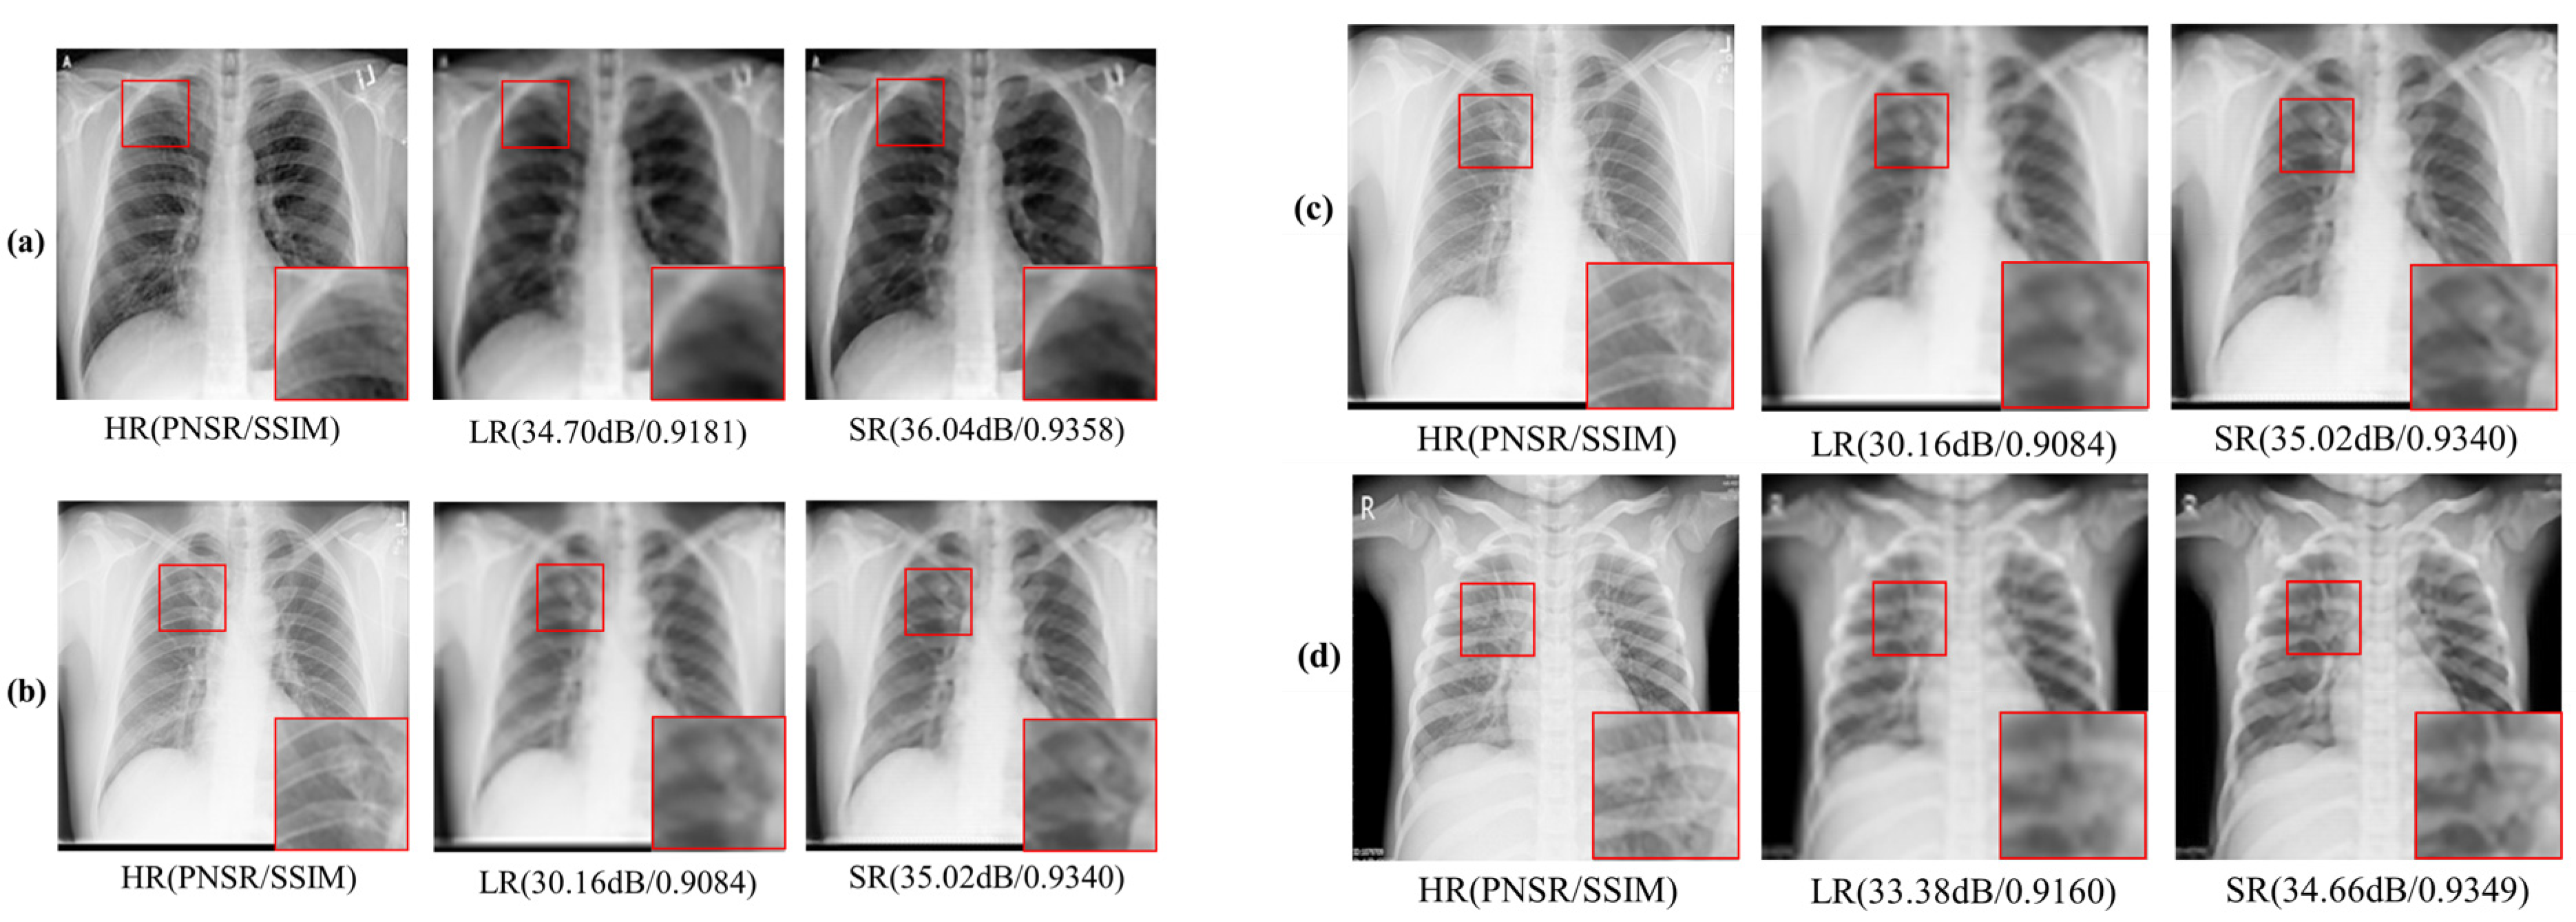

4. Experiments and Results